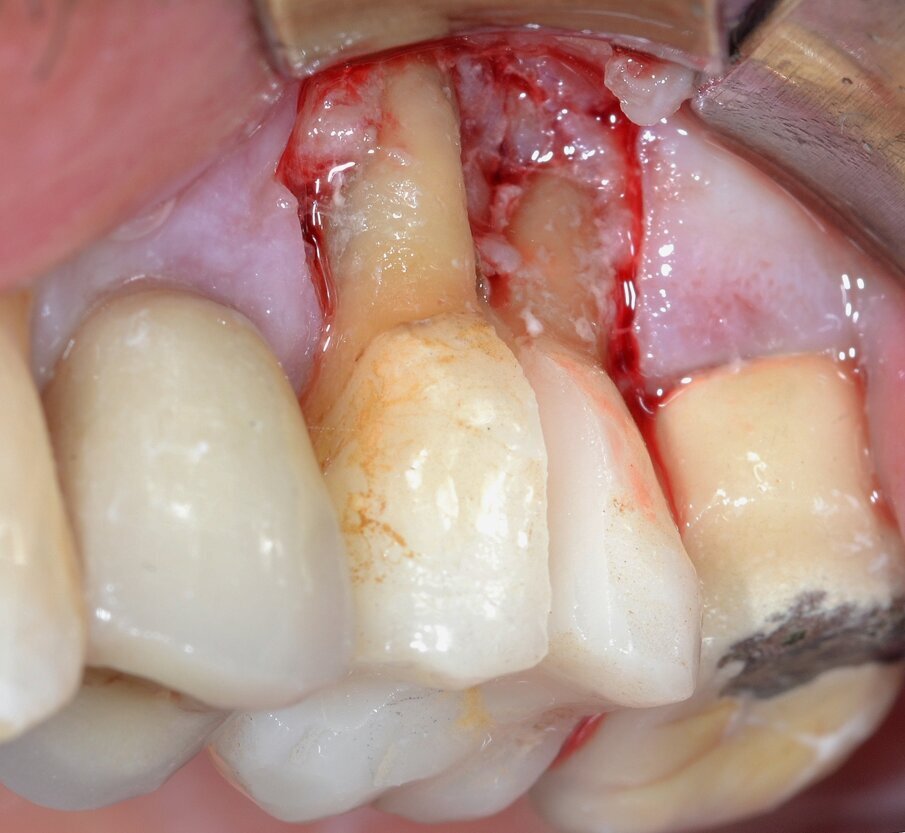

Il protocollo chirurgico di elezione consiste nell’eliminazione della forcazione stessa tramite procedura di rizectomia (ossia la sezione del complesso radicolare con l’eliminazione della/e radici giudicate non mantenibili) associata a resezione ossea e riposizionamento apicale del lembo: il complesso radicolare residuo sarà poi finalizzato mediante una protesi di tipo fisso. Dopo aver effettuato un’analgesia locale per infiltrazione con Articaina 1:100.000 con vasocostrittore si procede al sollevamento di un lembo a tutto spessore con lo scopo di accedere alla lesione parodontale: è possibile rilevare un importante difetto osseo che coinvolge la forcazione buccale (Fig. 4). La separazione delle due radici viene effettuato mediante frese diamantate o al carburo di tungsteno montate su manipolo ad alta velocità o su turbina: la sezione inizia nella zona del tetto della forcazione e si approfondisce verso l’interno facendo attenzione che l’angolo di inclinazione della fresa sia coincidente con l’asse lungo del dente (Fig. 5). L’eliminazione della radice mesio-buccale (Fig. 6) permette di ispezionare visivamente lo stato del complesso radicolare residuo, le cui condizioni depongono per una prognosi favorevole al mantenimento dell’elemento dentario nel tempo (Fig. 7).

Fig. 4 - Lembo di accesso a spessore totale: coinvolgimento della forcazione radicolare buccale di Classe 3 secondo Hamp & Nyman.